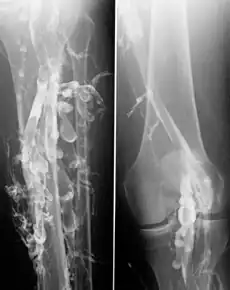

![]() 深静脉血栓病人的静脉成像。 | |